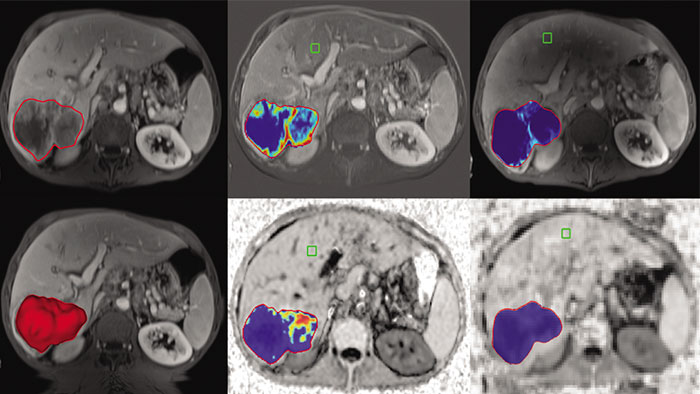

Tumor Tracking qEASL

Multi Modality Tumor Tracking qEASL (MMTT qEASL)

Semi-automatic tumor quantification

This semi-automated 3D (Volumetric) tumor response assessment tool, based on EASL (European Association for the Study of the Liver) criteria incorporates functional information from contrast-enhanced scans.

• Multi Modality Tumor Tracking supports the creation of Quantitative EASL (qEASL) maps used to measure segmented volumes of interest (VOI) in heterogeneous lesions.

• Data are presented as color map overlaid on the scans to show regional tumor enhancement heterogeneity. The color regions of the segmented lesions are where there is more enhancement than the pre-defined reference region.